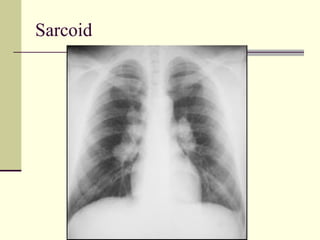

Hilar Adenopathy   1. Sarcoid 2. TB  3. Lymphoma  4. Bronchogenic ca  5. Mets

Sarcoid